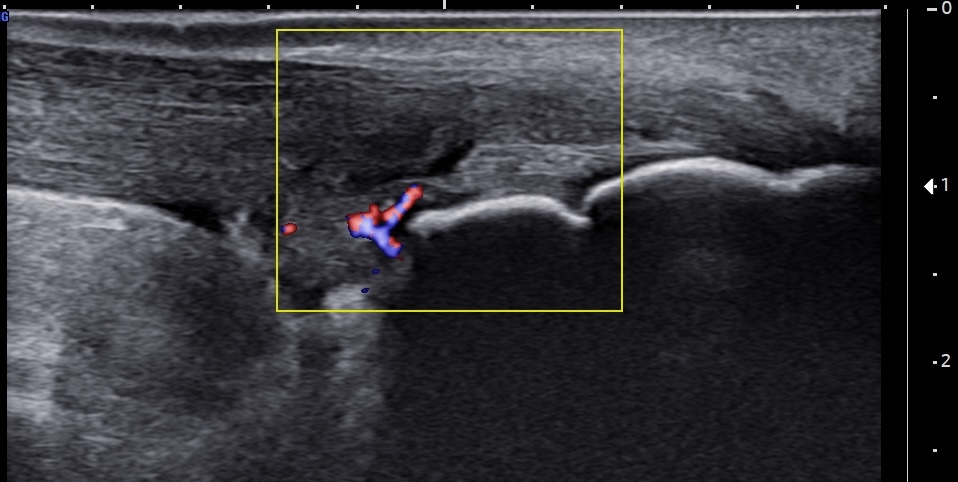

Short-axis ultrasound image of the pre-insertional Achilles tendon, a few millimeters proximal to the superior edge of the calcaneus, using color Doppler, demonstrating multiple neovessels within the retrocalcaneal bursa and the deep fibers of the tendon. Notably, the Doppler signal appears more prominent in the short-axis view compared to the long-axis images.

Unlabeled long-axis ultrasound image of the insertional and pre-insertional Achilles tendon using color Doppler, demonstrating a few neovessels at the retrocalcaneal bursa and within the deep tendon fibers, consistent with chronic bursitis and tendinopathy.